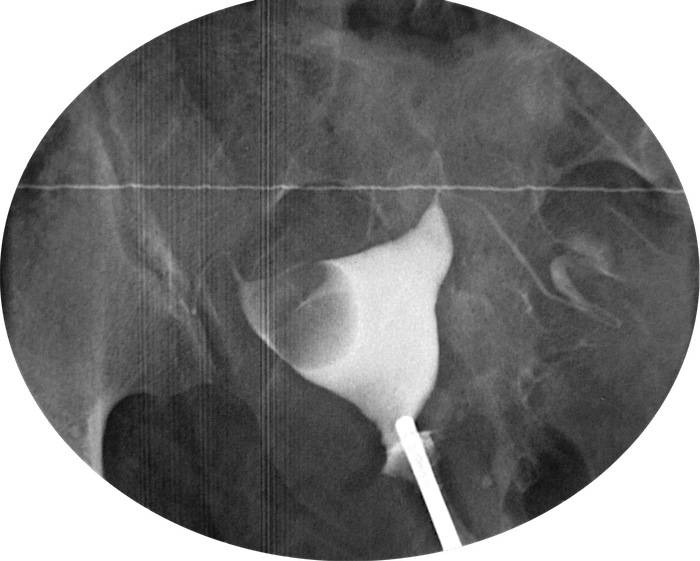

Медицинские снимки: Проходимость маточных труб

Раздел: Кадры-подсказки